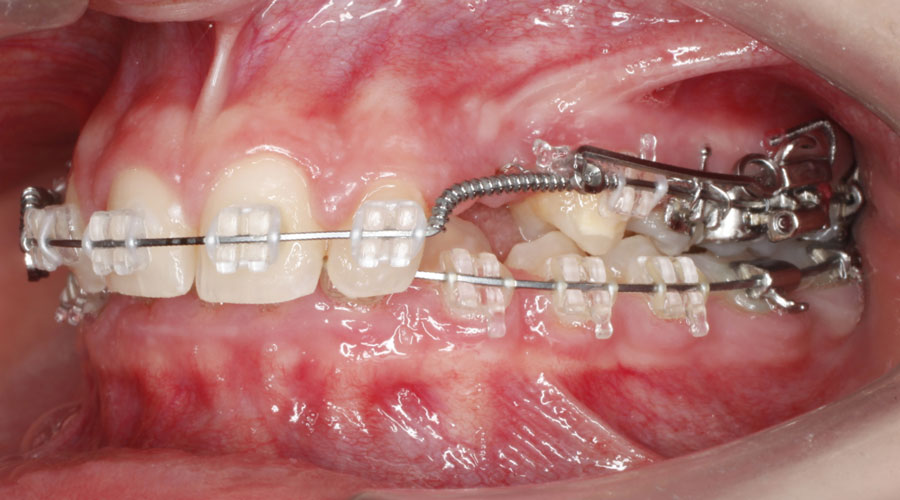

Caso clínico 2. La paciente presentaba Clase II dentaria división 2ª, con gran sobremordida, además de erupción ectópica de los caninos superiores. Se realizó ortodoncia multibracket transparentes con cirugía de fenestración de ambos caninos. Debido a la posición de éstos por palatino, colocamos dos microtornillos para ayudarnos en su tracción y poder separar la corona de las raíces de los incisivos. Posteriormente, traccionamos desde la cara vestibular con ayuda de un resorte para colocarlo en su lugar en la arcada.